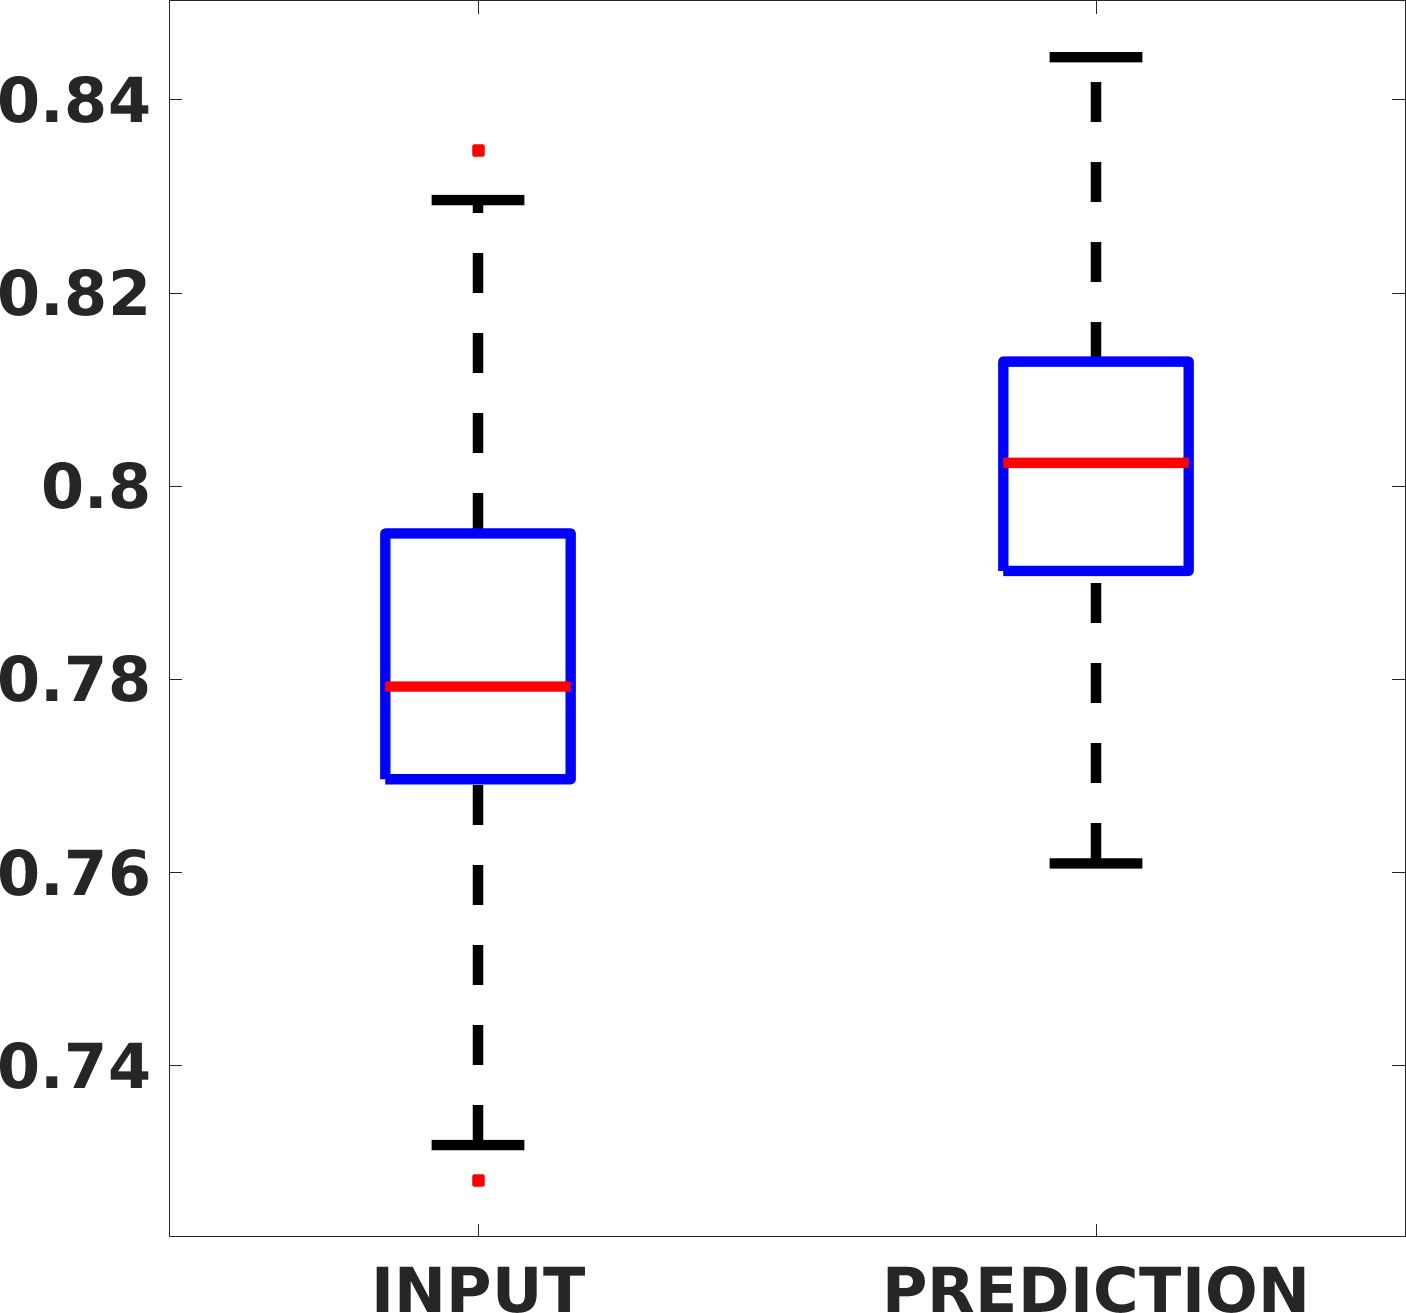

Fig. 8 shows the box plot of the SSIM (a-b-c, left) and MAE (a-b-c, right) quantitative metrics, as performed for PSNR metric. Also, these metrics show that our method improves the results of Cubic convolution both in terms of average value and variability. For example, the SSIM median value improves of on obstetric 4X images and the MAE median value improves of on cardiac 2X images.

Fig. 17 (left) shows the box plot of the quantitative metrics, comparing the target images with the prediction and the Cubic convolution, respectively. The PSNR metric is computed on a data set of 200 images, belonging to the same district, and with the same up-sampling factor. Analysing the obstetric anatomical district and concerning the corresponding raw images (Fig. 7 (a, left)), the denoising allows the network to significantly improve the results of the up-sampling and the prediction. In particular, comparing the target images with the predicted images, the median PSNR value of obstetric 2X denoised images is 51.8, compared to the median PSNR value of obstetric 2X raw images which is 36.9.

Fig. 17 (right) shows the histogram of the absolute value of the error with respect to the target, of the prediction and Cubic convolution respectively. This result shows that our framework increase of and (2X and 4X, respectively) the number of pixels where the prediction error is lower than 5, which is very similar to the target when visually analysing the images, and improved with respect to the learning framework applied to raw images. According to Fig. 18, our method improves the accuracy of Cubic convolution. For example, the SSIM increases of on cardiac 2X and the MAE increases of on abdominal 4X.